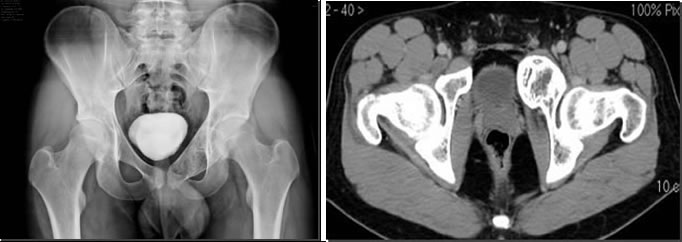

Prevalentemente la crescita è lenta, talvolta nelle forme aggressive, le cistiche aneurismatiche assumono un rapido sviluppo, raggiungendo rilevanti dimensioni tanto da essere definite simil sarcomatose. Tutte le ossa possono essere colpite, tuttavia sono interessate con maggior frequenza le metafisi delle ossa lunghe e le vertebre.

La sintomatologia è di solito rappresentata da tumefazione e dolore, peraltro di grado lieve, la struttura ossea interessata assume un aspetto osteolitico marcato, talora rilevante, le fratture patologiche sono rare.

Le suddette lesioni presentano una ipervascolarizzazione patologica rifornita da uno o più vasi e sono caratterizzate dalla presenza di cavità incluse ripiene di detriti cellulari e sangue, separate da setti connettivali, sono tipici i livelli liquidi ben visibili alla TC ed alla RM.

Adolescente di 16 anni.